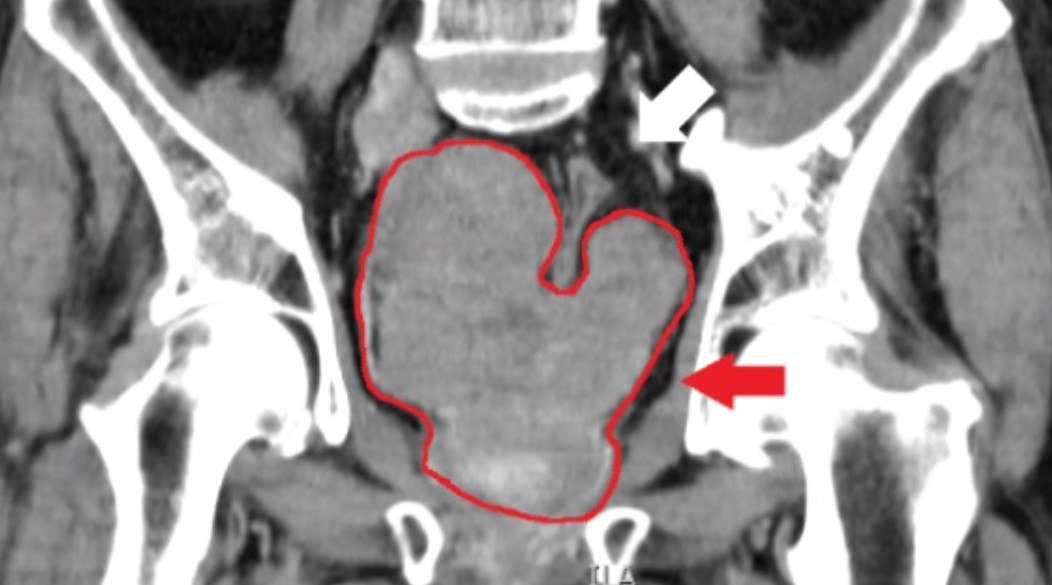

By Andy Ford, biomedical scientist and Unite member The decision from the UK National Screening Committee not to offer prostate cancer screening to high-risk men